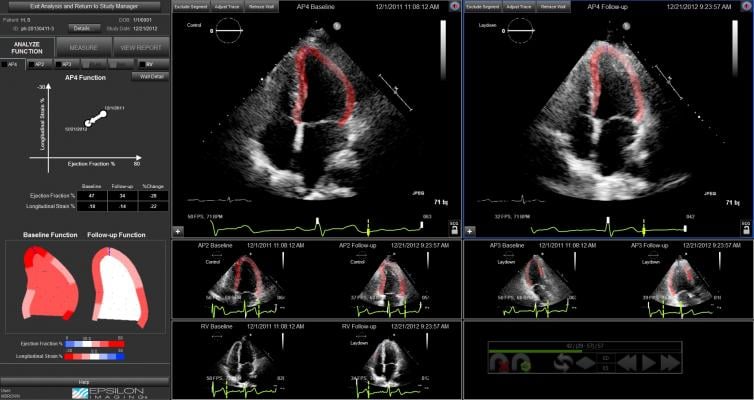

Thirty-four patients with human epidermal growth factor receptor 2 (HER2)-positive breast cancer who were treated with non-anthracycline trastuzumab-based regimens at a single center underwent standard echo studies prior to starting chemotherapy, and again at three-month intervals during therapy. Two-dimensional speckle-tracking strain was retrospectively obtained using EchoInsight software. The results of the study showed 10 patients developing cardiotoxicity during therapy. A significant reduction in global longitudinal strain (GLS) preceded the decrease in LVEF. A significant decrease in global circumferential strain (GCS) was demonstrated after a change in GLS.